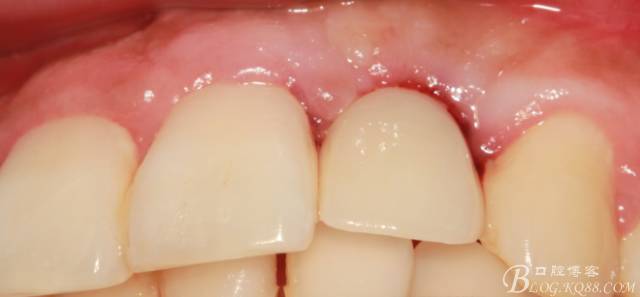

4個(gè)月后,唇側(cè)豐滿度尚可,與鄰牙之間齦乳頭完整。

戴入永久修復(fù)體當(dāng)天口內(nèi)照,雖有小瑕疵,但患者很滿意。